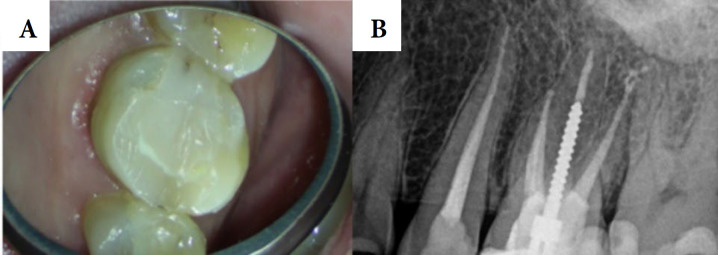

The patients with unusual symptoms present a diagnostic challenge for clinicians and may lead to misdiagnoses and inappropriate or unnecessary treatments. Endodontic diseases can present with a variety of symptoms, and it is possible for odontogenic pain to resemble non-odontogenic pain, which can complicate treatment due to the distinct management plans of the two conditions. This report details the successful management of vague pain, and popping sensations in the left maxilla triggered by cold exposure. Previous clinicians were unable to identify the pain's origin, leading to unnecessary treatments. A clinical examination, and cone-bean computed tomography evaluation revealed the presence of a missed second mesiobuccal root canal. The canal was located using an operating microscope and ultrasonics. Non-surgical endodontic retreatment was completed in two visits, successfully. This report highlights the critical importance of identifying the diverse symptoms that may arise from endodontic origin, as these can complicate clinical diagnosis.